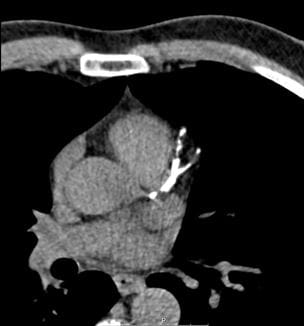

Experience at University Hospitals Cleveland Medical Center Shows Effectiveness of Pulmonary Embolism Response Team Approach

PERT members also launching clinical trials of new interventional devices, studying use - Innovations in Pulmonology & Sleep Medicine